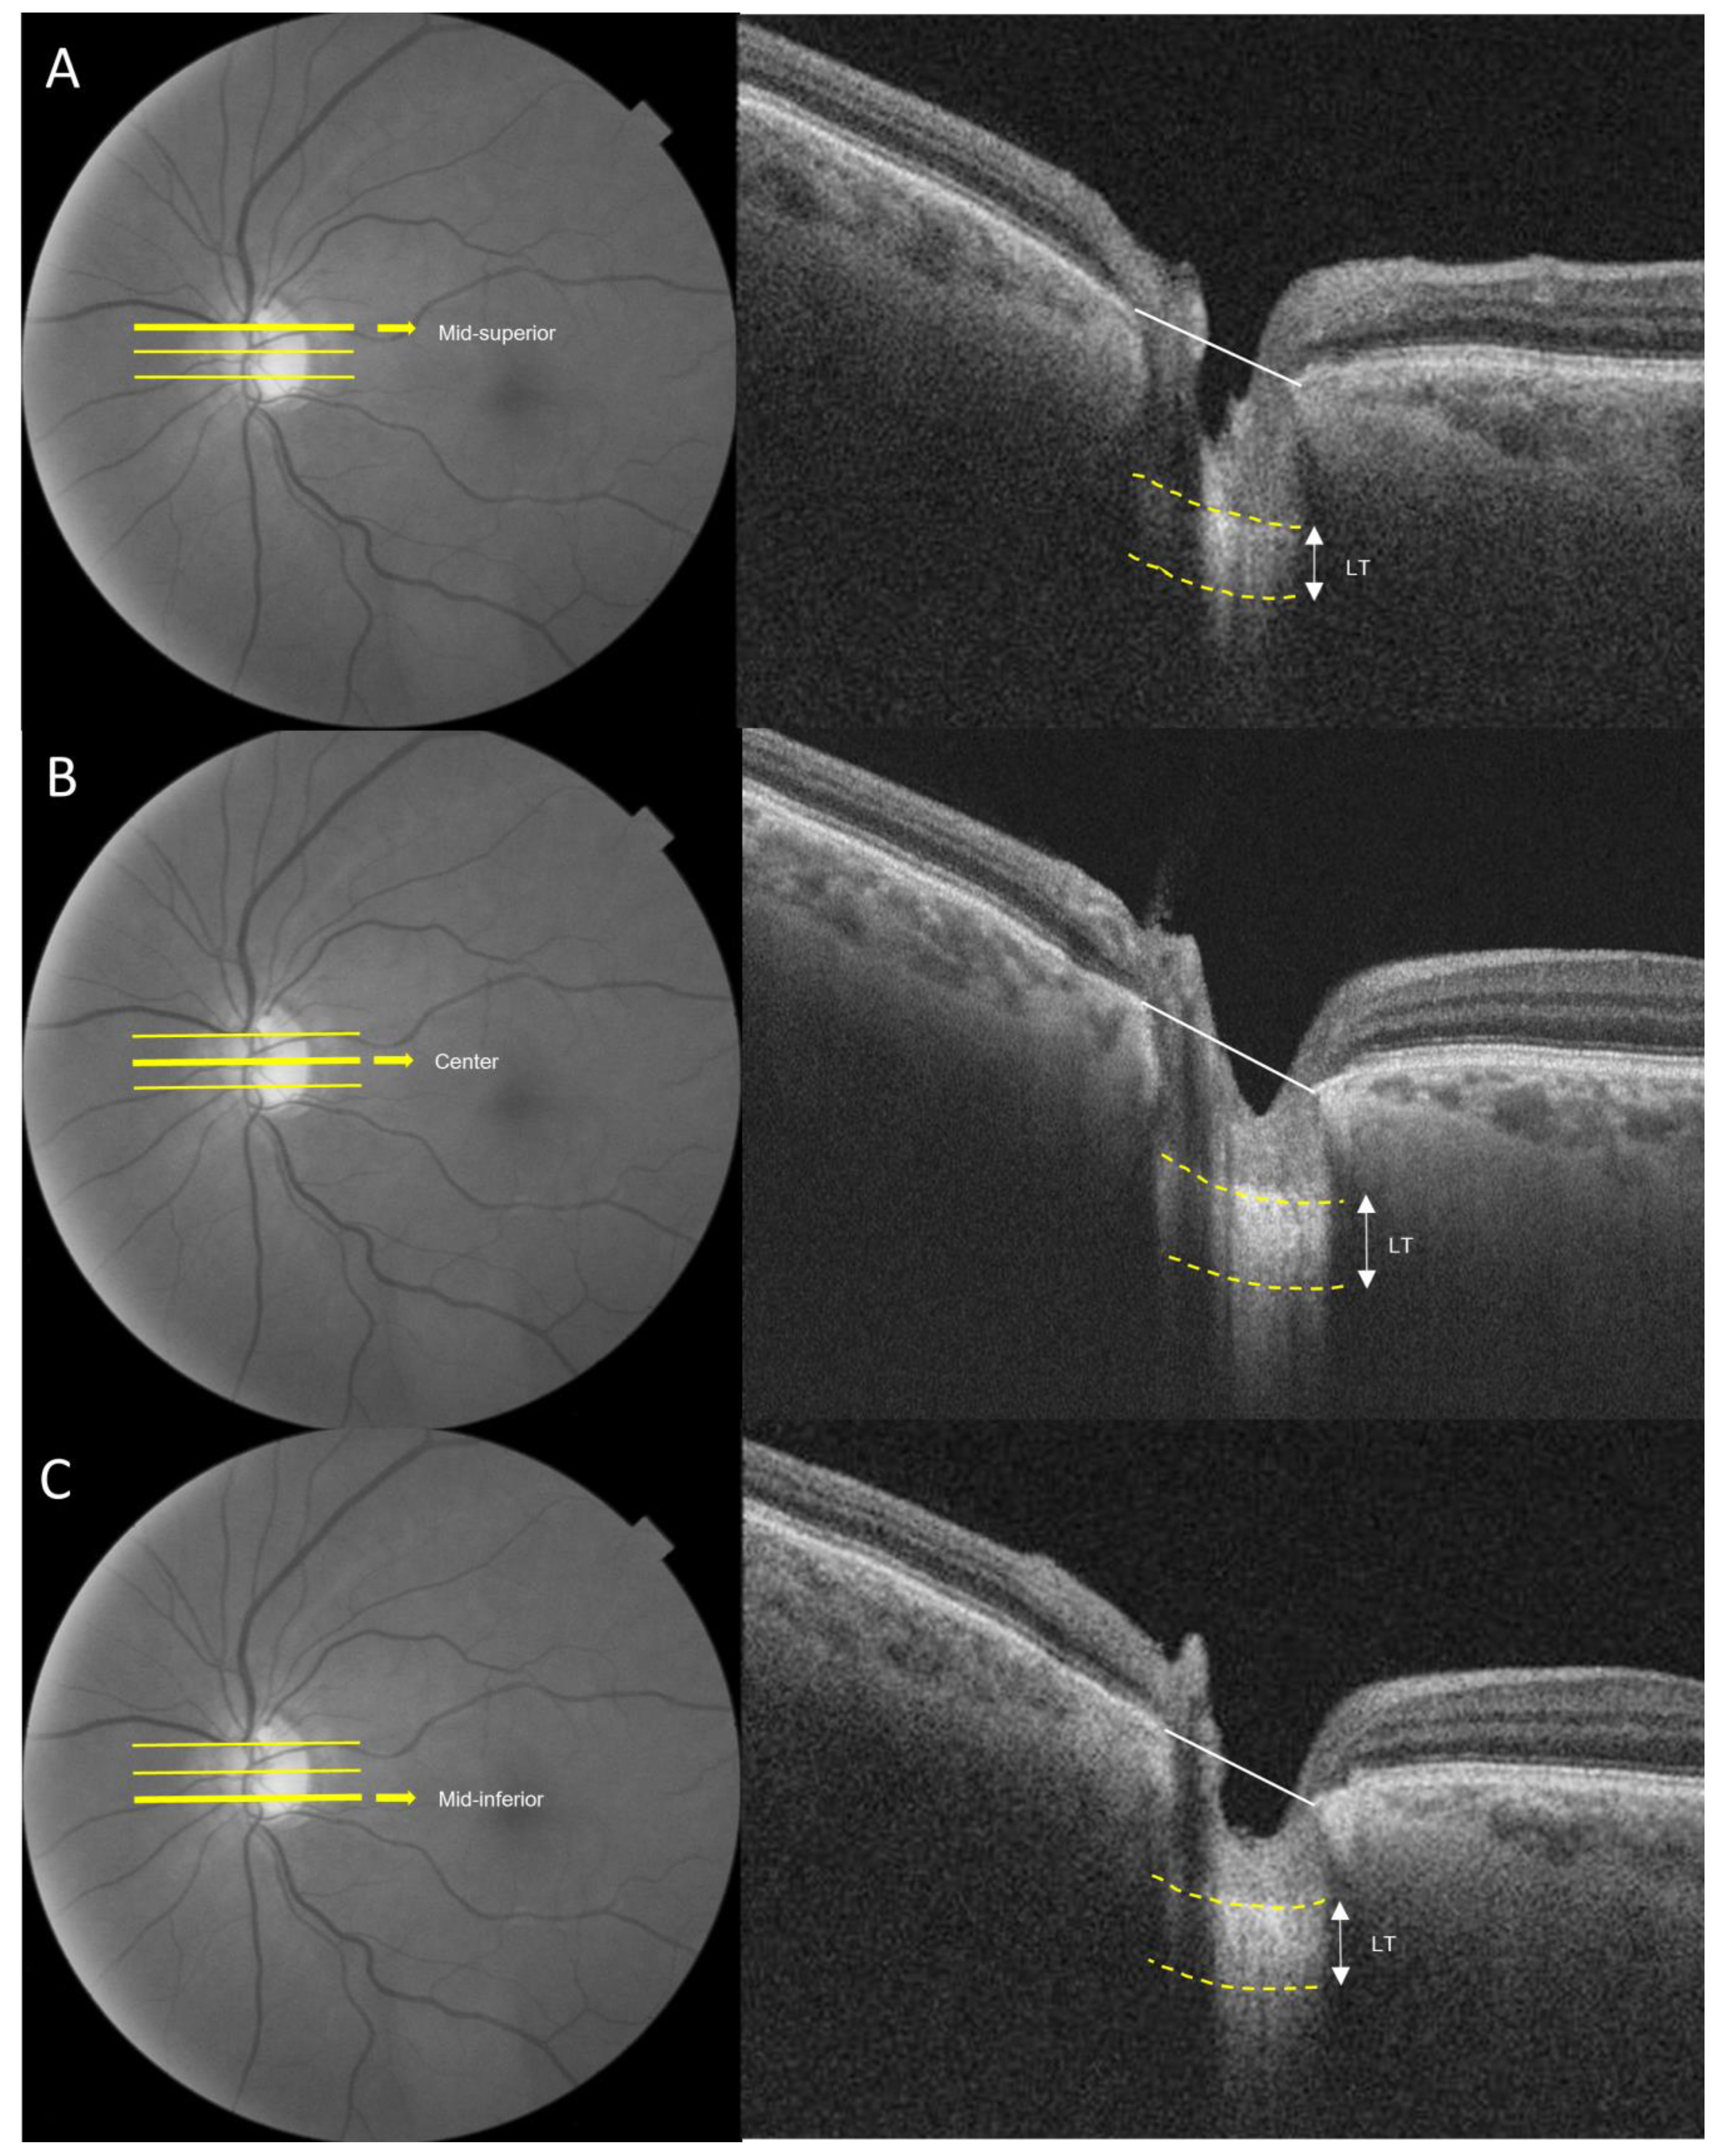

2.5. Laminar Cribrosa Assessment by SS-OCT

| Lamina Cribrosa Thickness | |||

| Mid-superior, μm | 176.16 ± 22.74 | 151.66 ± 20.88 | <0.001 |

| Center, μm | 188.50 ± 29.21 | 176.63 ± 24.70 | 0.084 |

| Mid-inferior, μm | 171.19 ± 31.70 | 151.25 ± 22.31 | 0.005 |

| Mean, μm | 178.61 ± 15.74 | 159.84 ± 15.60 | <0.001 |